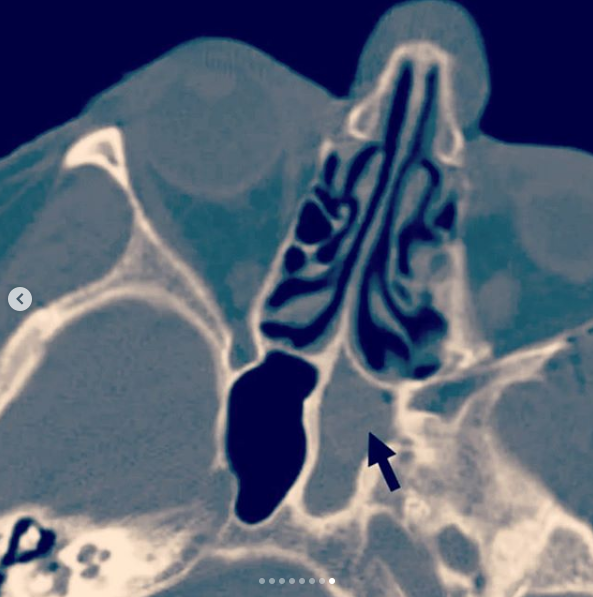

Сфеноидит симптомы